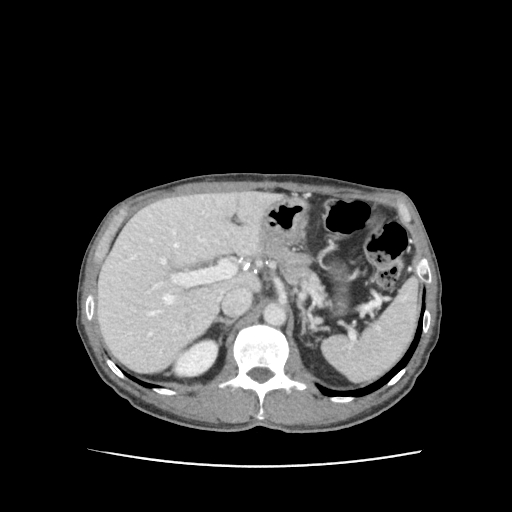

초음파로 간·담낭·담도·췌장·비장·신장·대동맥 등 복부 장기를 평가하는 비침습 검사입니다.

2. 간염 & 간농양 &간암

피로감, 미열, 우상복부의 뻐근한 불편감, 그리고 황달이 특징입니다. 간농양은 고열과 심한 통증이 동반되고 응급 처치가 필요한 경우도 있습니다.